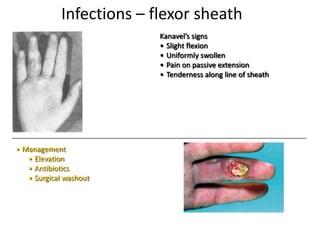

- Conditions that require emergency referral are discussed, such as bleeding, amputation, replantation, compartment syndrome, infections, and high pressure injection injuries. Proper management of these conditions focuses on rapid assessment and treatment to prevent further tissue damage.